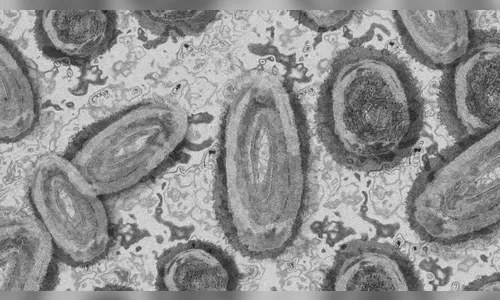

Autor Conforme o novo boletim, não há óbitos ocasionados pela doença no Estado - Foto: Foto ilustrativa/Pixabay

A Mpox é uma doença viral, e a transmissão entre humanos ocorre principalmente por meio de contato com lesões de pele de pessoas infectadas. A infecção causa erupções que geralmente se desenvolvem pelo rosto e depois se espalham para outras partes do corpo. Os principais sintomas envolvem febre, dor de cabeça, dores musculares, dores nas costas, linfadenopatia, calafrios e fadiga.